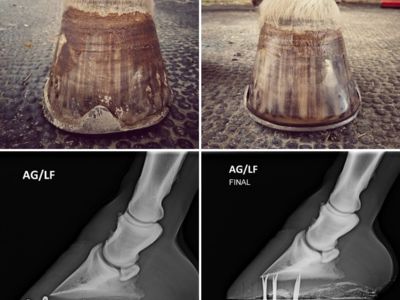

Galerie

photo account presentation